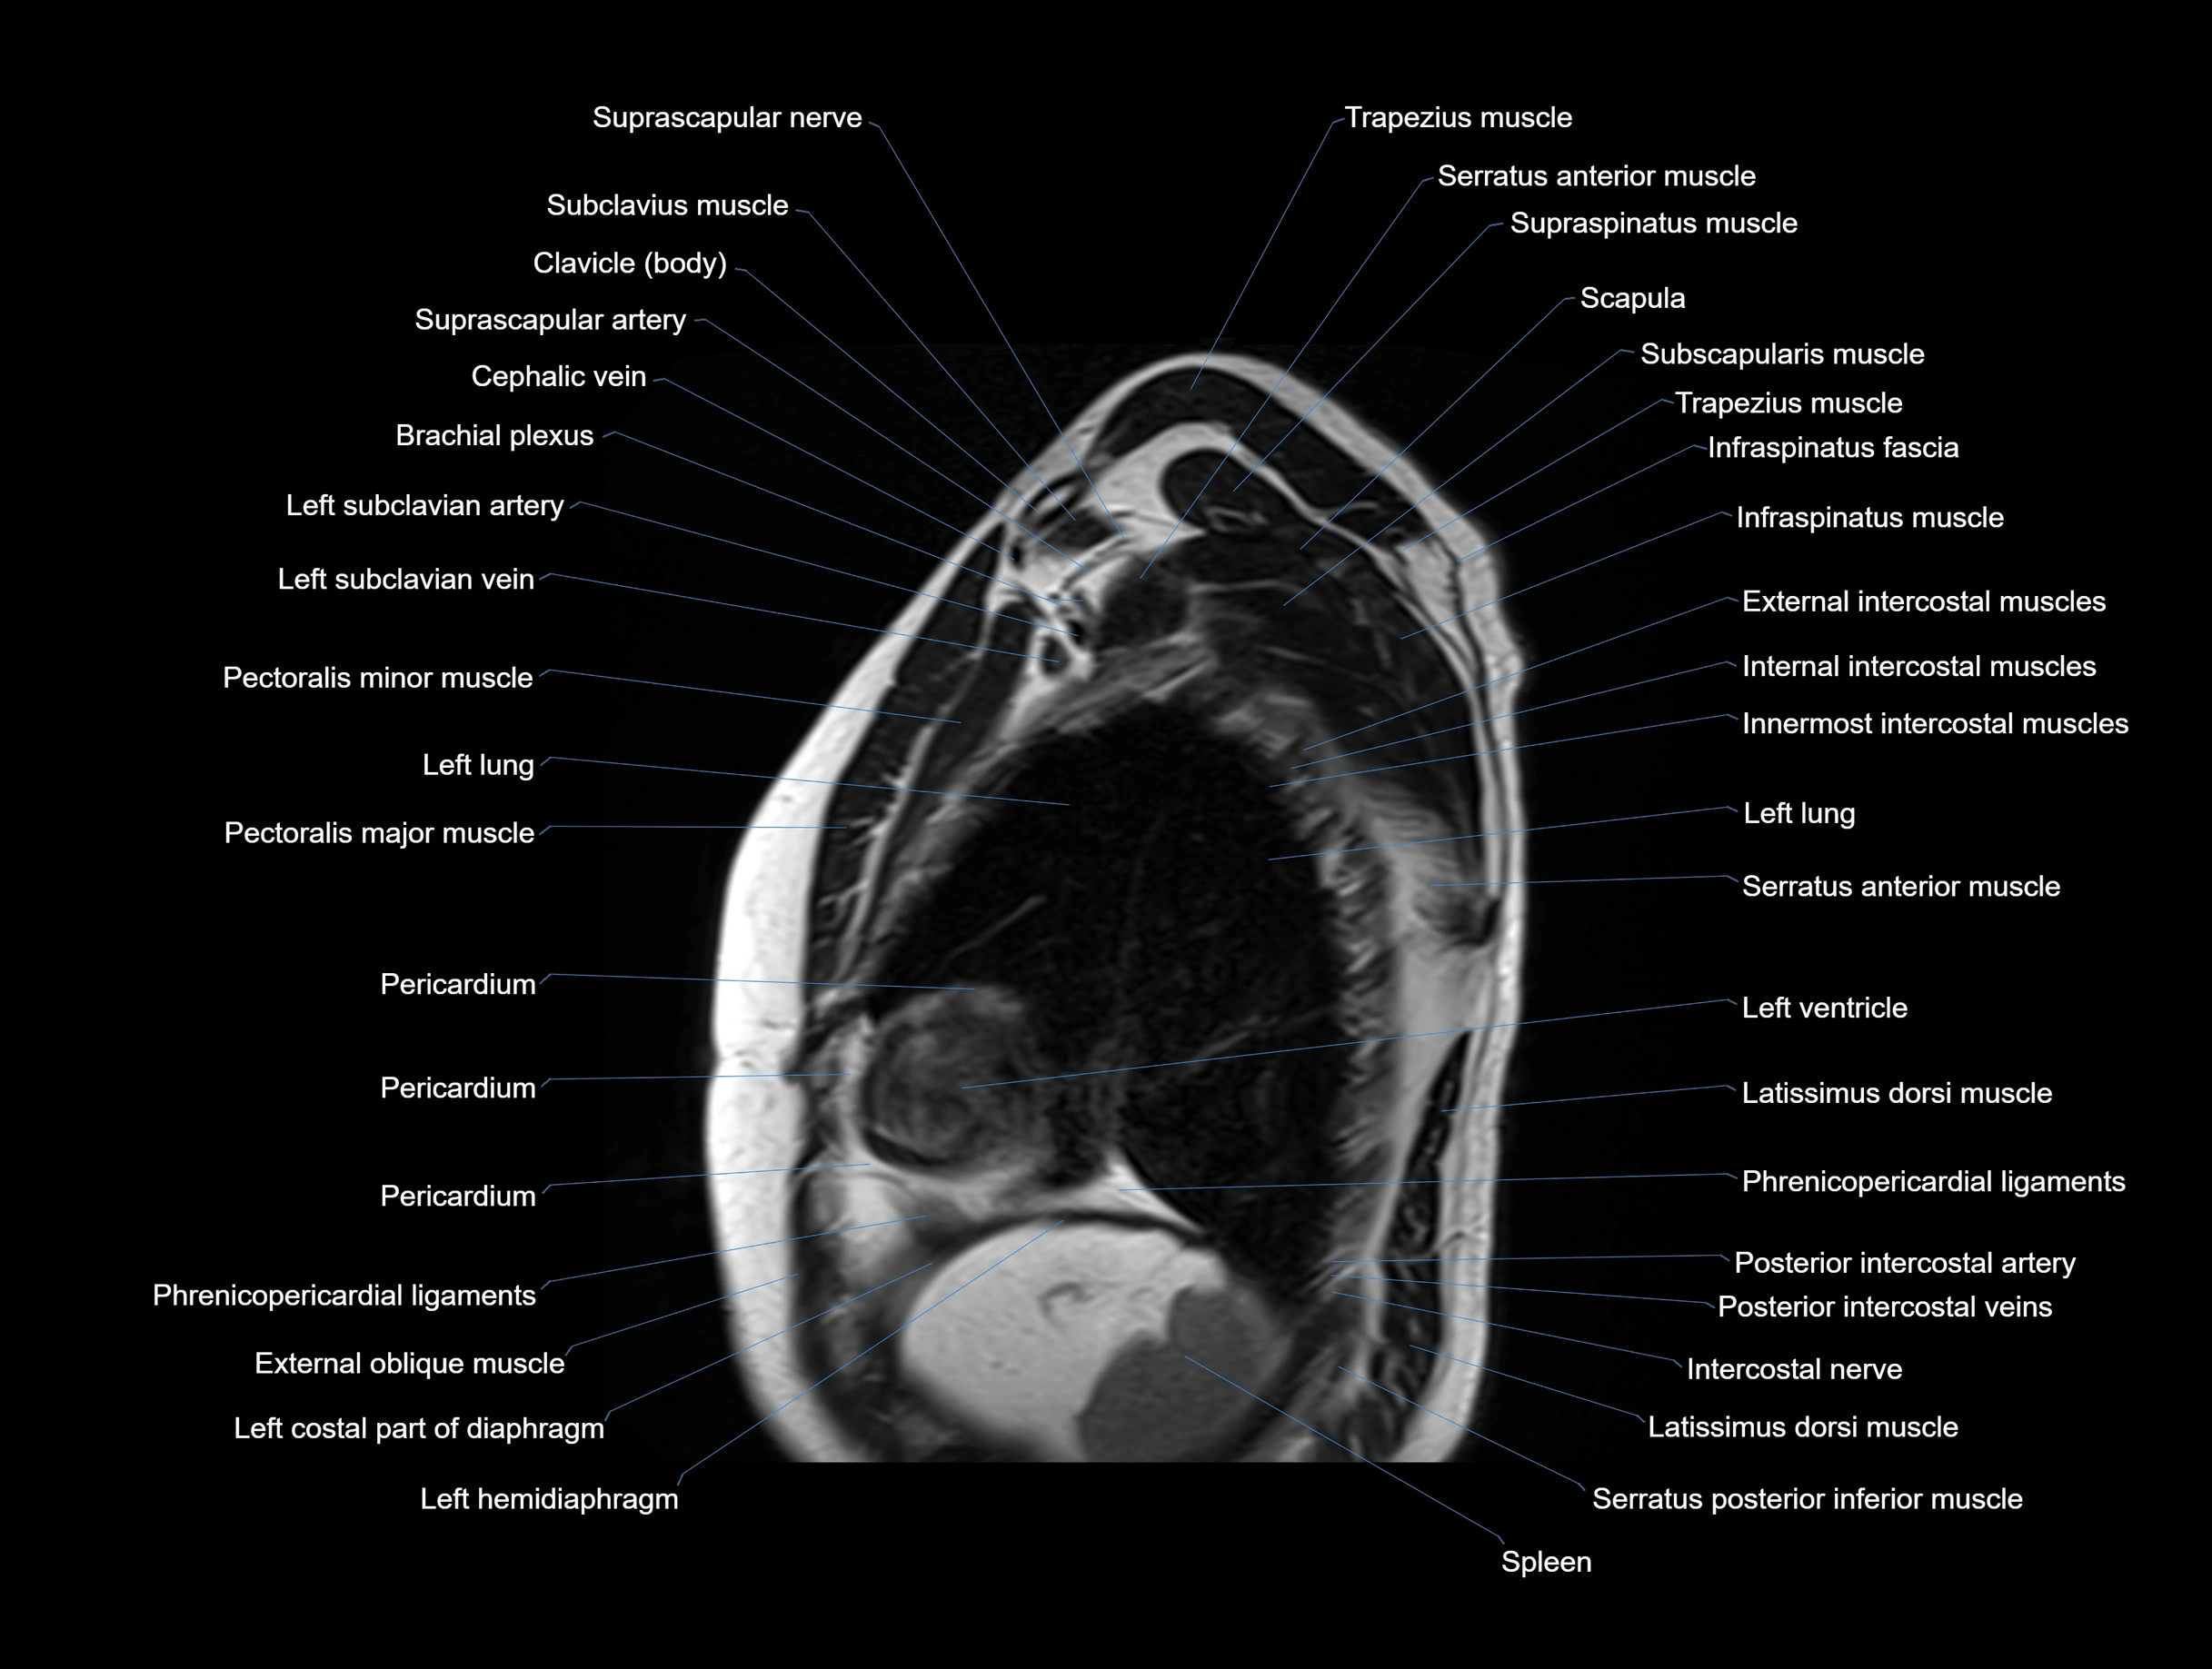

MRI images